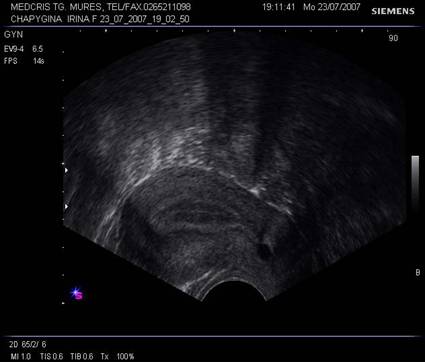

2.Explorarea ecografica transvaginala

Se realizeaza cu sonde dedicate, acoperite cu un prezervativ. Are aproximativ aceleasi aplicatii ca si ecografia transabdominala a micului bazin, in schimb datorita eliminarii peretelui abdominal dintre sonda si organele genitale interne, ca si posibilitatile utilizarii de frecvente mai mari, detaliile de ecostructura sunt mult mai bune. Nu trebuie uitat ca unele paciente nu pot fi examinate transvaginal (de exemplu virgine, unele anomalii genitale,operatii anterioare, etc) de aceea anamneza si consultul genital ar trebui sa preceada explorarea ecografica.Vezica urinara va fi spre stanga imaginii in sectiunea sagitala a pelvisului, conventional sectorul sondei se va deschide de jos in sus. Exista si scoli de ecografie care pastreaza alte conventii de pozitionare a sondei.Pozitia uterului de anteflexie sau retroversoflexie trebuie identificata , preferabil a fi cunoscuta inainte de inceperea ecografiei transvaginale.